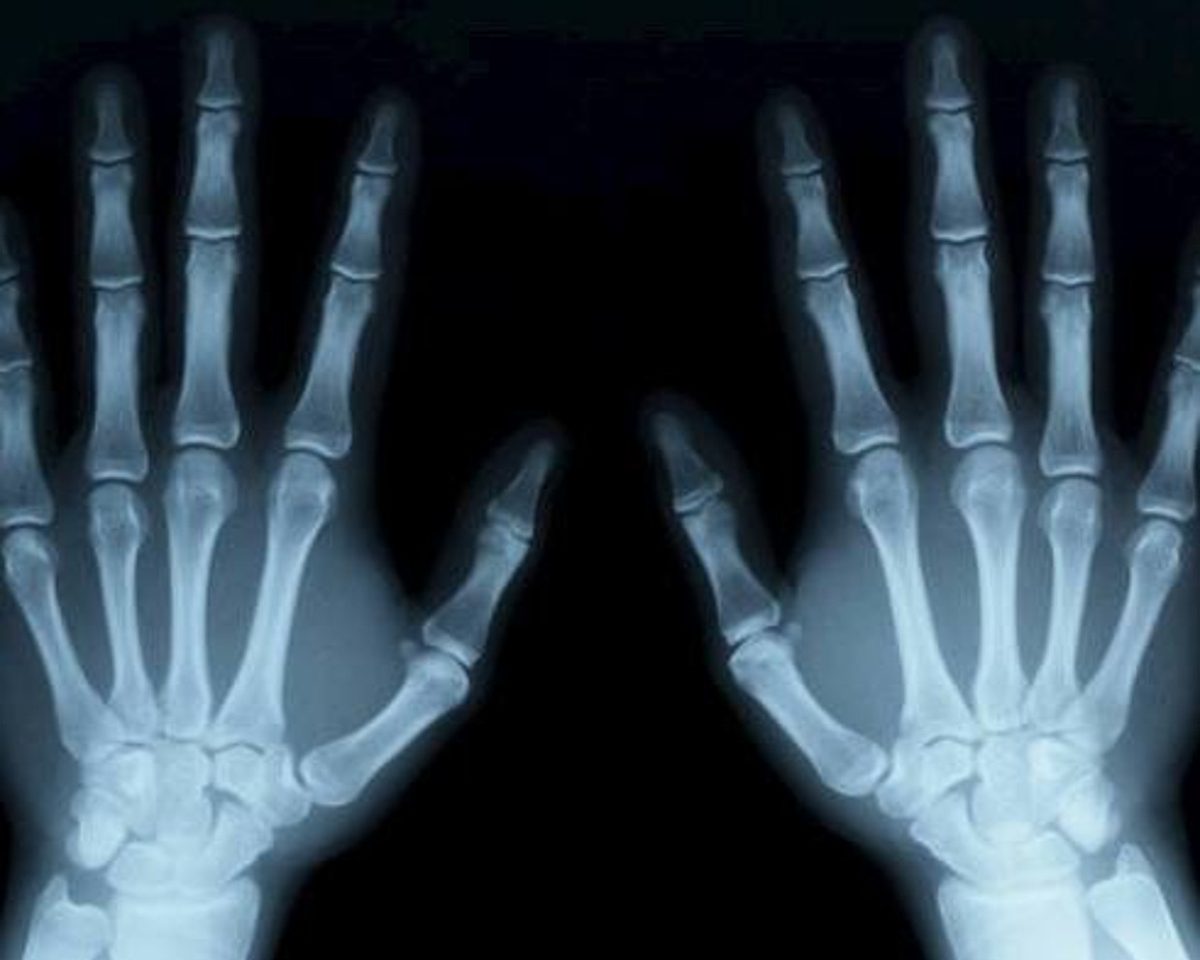

The medical industry is experiencing exponential growth in everything sensors and the range of imaging sensors used in medical applications is wide: from extra compact cameras (i.e. for endoscopes) up to huge x-ray sensor arrays, visible light over Infra Red (IR) to different tomography sensors like X-ray & CT, Ultrasonic, Magnetic Resonance (MRT), Positron Emission (PET) and others.